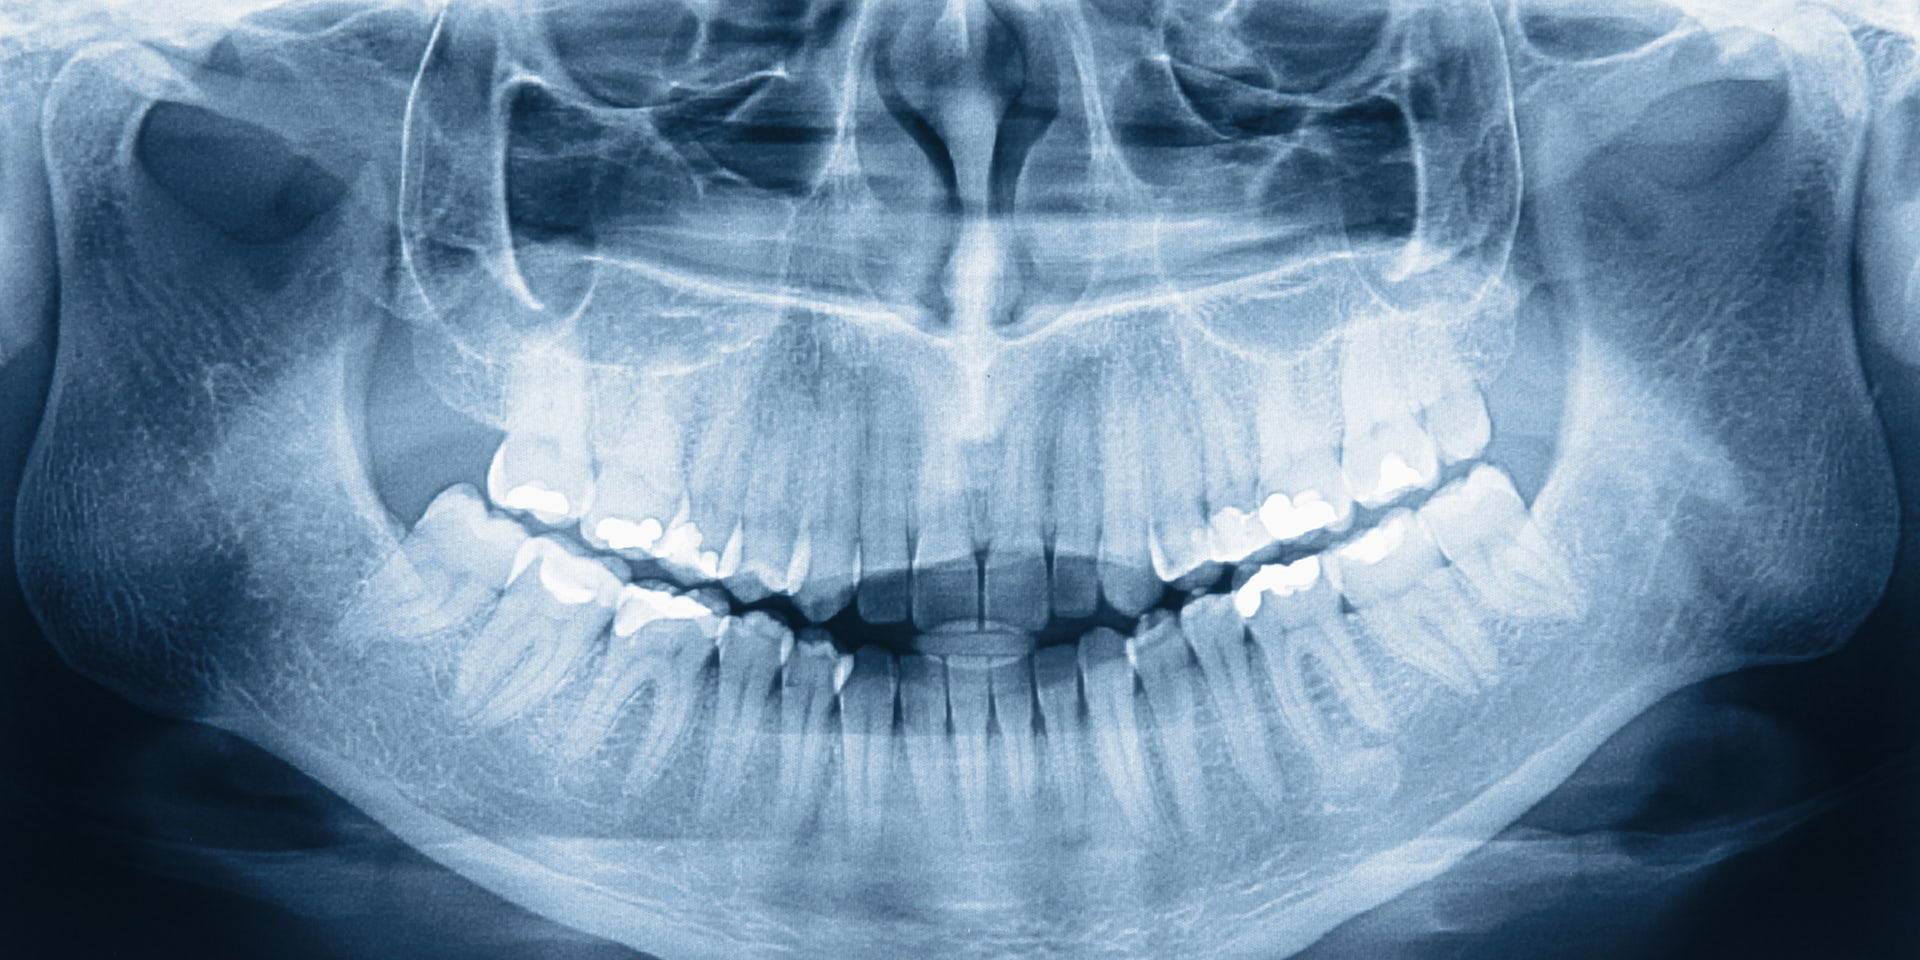

Панорамная томография (ортопантомограмма, ОПТГ)

это метод рентгеновской съёмки, позволяющий получить развёрнутое на плоскости панорамное изображение всех зубов, челюстей и прилежащих к ним отделов лицевого скелета.

По нему врач с достаточной степенью точности может оценить состояние каждого зуба, костной ткани челюстей, височно-нижнечелюстных суставов, гайморовых пазух.

ОПТГ или панорамная томограмма — это своеобразный «золотой стандарт» в стоматологической рентгенодиагностике. Она позволяет оценить состояние зубочелюстной системы. Цифровой ортопантомограф предоставляет врачу-стоматологу подробную информацию о твердых тканях зубочелюстной системы, а также о состоянии височно-нижнечелюстных суставов и гайморовых пазух. По одному единственному панорамному снимку врач может определить состояние костной ткани, наличие или отсутствие пломбировочных материалов, непрорезавшихся зубов, кист, опухолей, скрытых кариозных полостей и очагов воспаления в околокорневых тканях.

Общее состояние челюсти и близлежащих тканей, расположение корней зубной системы и других ее фрагментов — все это показывает ОПТГ.

Что видно на панорамном снимке зубов?

Плотные вещества (такие как пломбы или металлические коронки) блокируют излучение рентгеновских лучей, поэтому на изображении они получаются белыми. Зубы и ткани обозначены разными оттенками серого.

В частности, анализ изображения показывает:

- общий вид зубов;

- поражены ли корни зуба кариесом;

- полости соприкосновения зубов;

- кисты, гранулемы, непрорезавшиеся зубы;

- новообразования в челюстной кости;

- состояние гайморовых пазух.